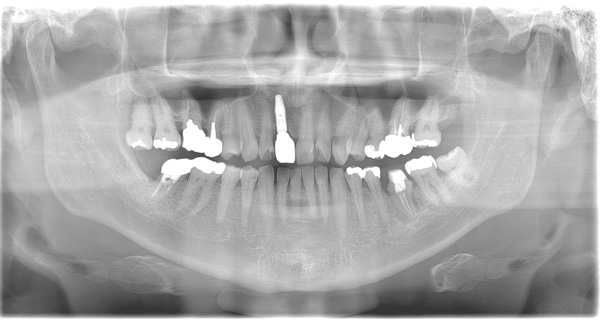

BEFORE

| 年代・性別 | 50代 女性 |

|---|---|

| 主訴 | 左上のブリッジがグラグラして外れそう |

| 治療期間 | 約18ヶ月 |

| 費用 | 1,600,000円 |

| 治療内容 | インプラント、骨造成、サイナスリフト、セラミック修復 |

| 治療に伴うリスク | インプラント周囲炎 セラミックの破折、脱離 |